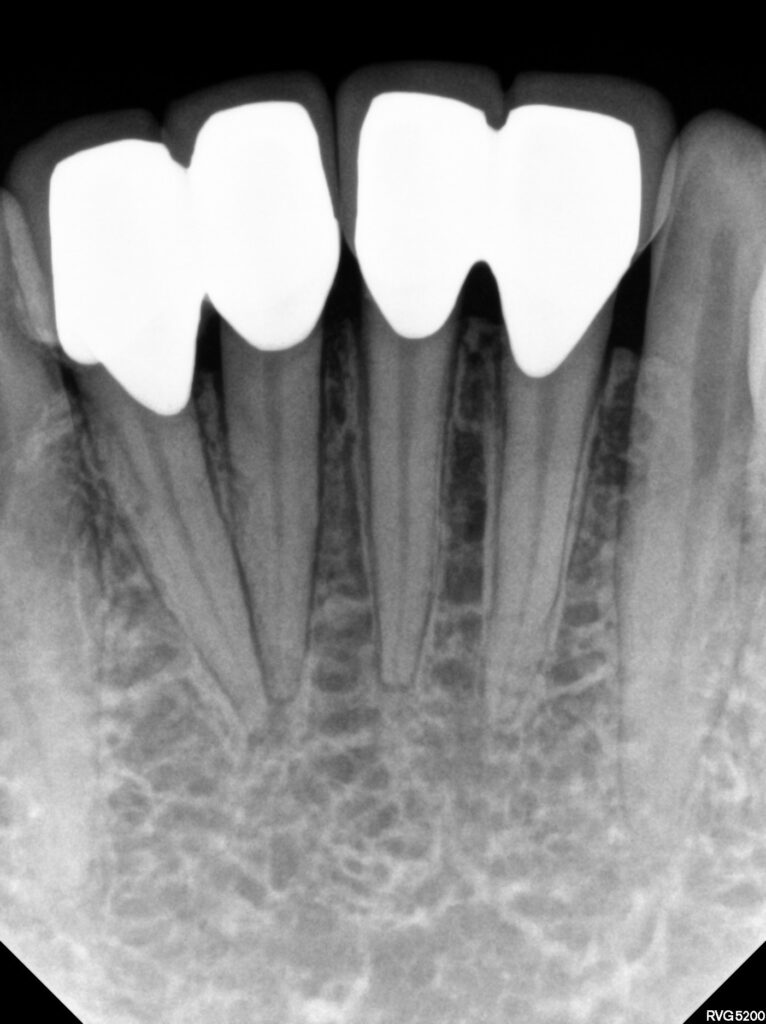

4개의 치아 중 문제가 있는 치아를 감별하기 위해

러버댐으로 치아를 격리하고 ICE / Hot test 시행하여

감별진단하였습니다.

기존 보철물의 경우 두개씩 치아를 연결해

치아 사이사이 관리가 잘 되지 않아

잇몸 반응도 좋지 않아 붉은 염증이 계속되고

있는 점도 확인하였는데요.

모든 크라운을 제거해보니 이전 치과에서

너무 치아삭제를 많이 해서 치수염이 발생했던 것으로

판단되었습니다.